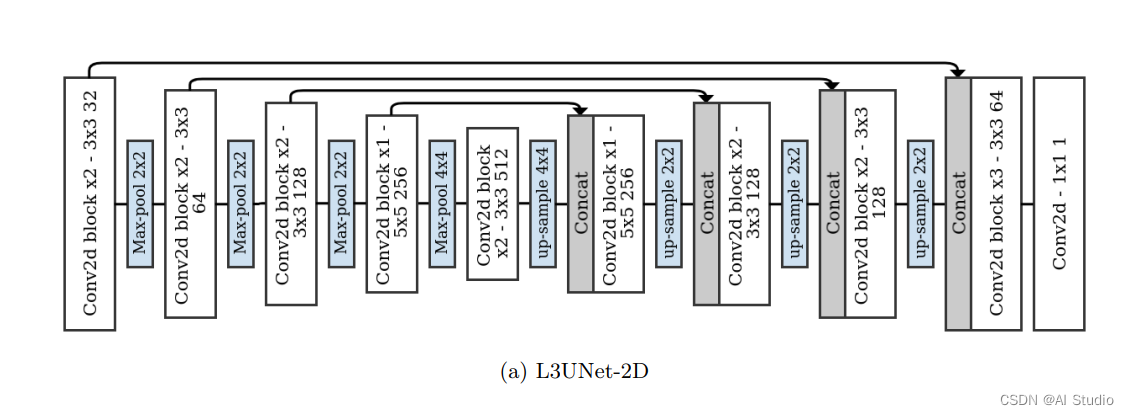

该文章提出了一种在三维CT图像中自动检测L3切片的有效方法。适用于具有各种视场、遮挡和切片厚度的图像。

然后将MIP图像用作2D全卷积网络的输入,以2D置信图的形式预测L3切片的位置。

将2D MIP图像用作网络的输入。根据网络,输出是1D或2D置信图。